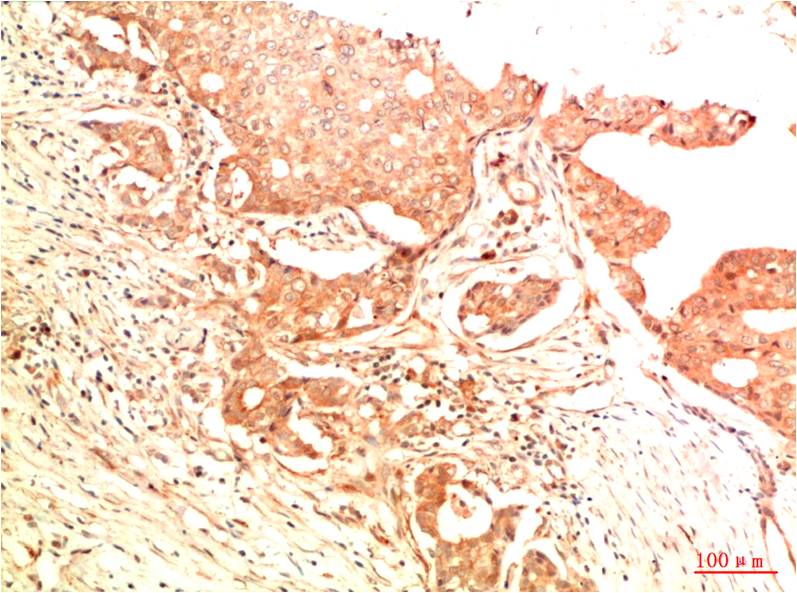

Acetyl P53(K382) Mouse Monoclonal Antibody(5H10)

Applications :IHC

| Recommended dilutions: | IHC: 1:100-200 |

| Specificity: | The Acetyl P53(K382) Mouse Monoclonal Antibody can detects endogenous Acetyl P53(K382) proteins. |